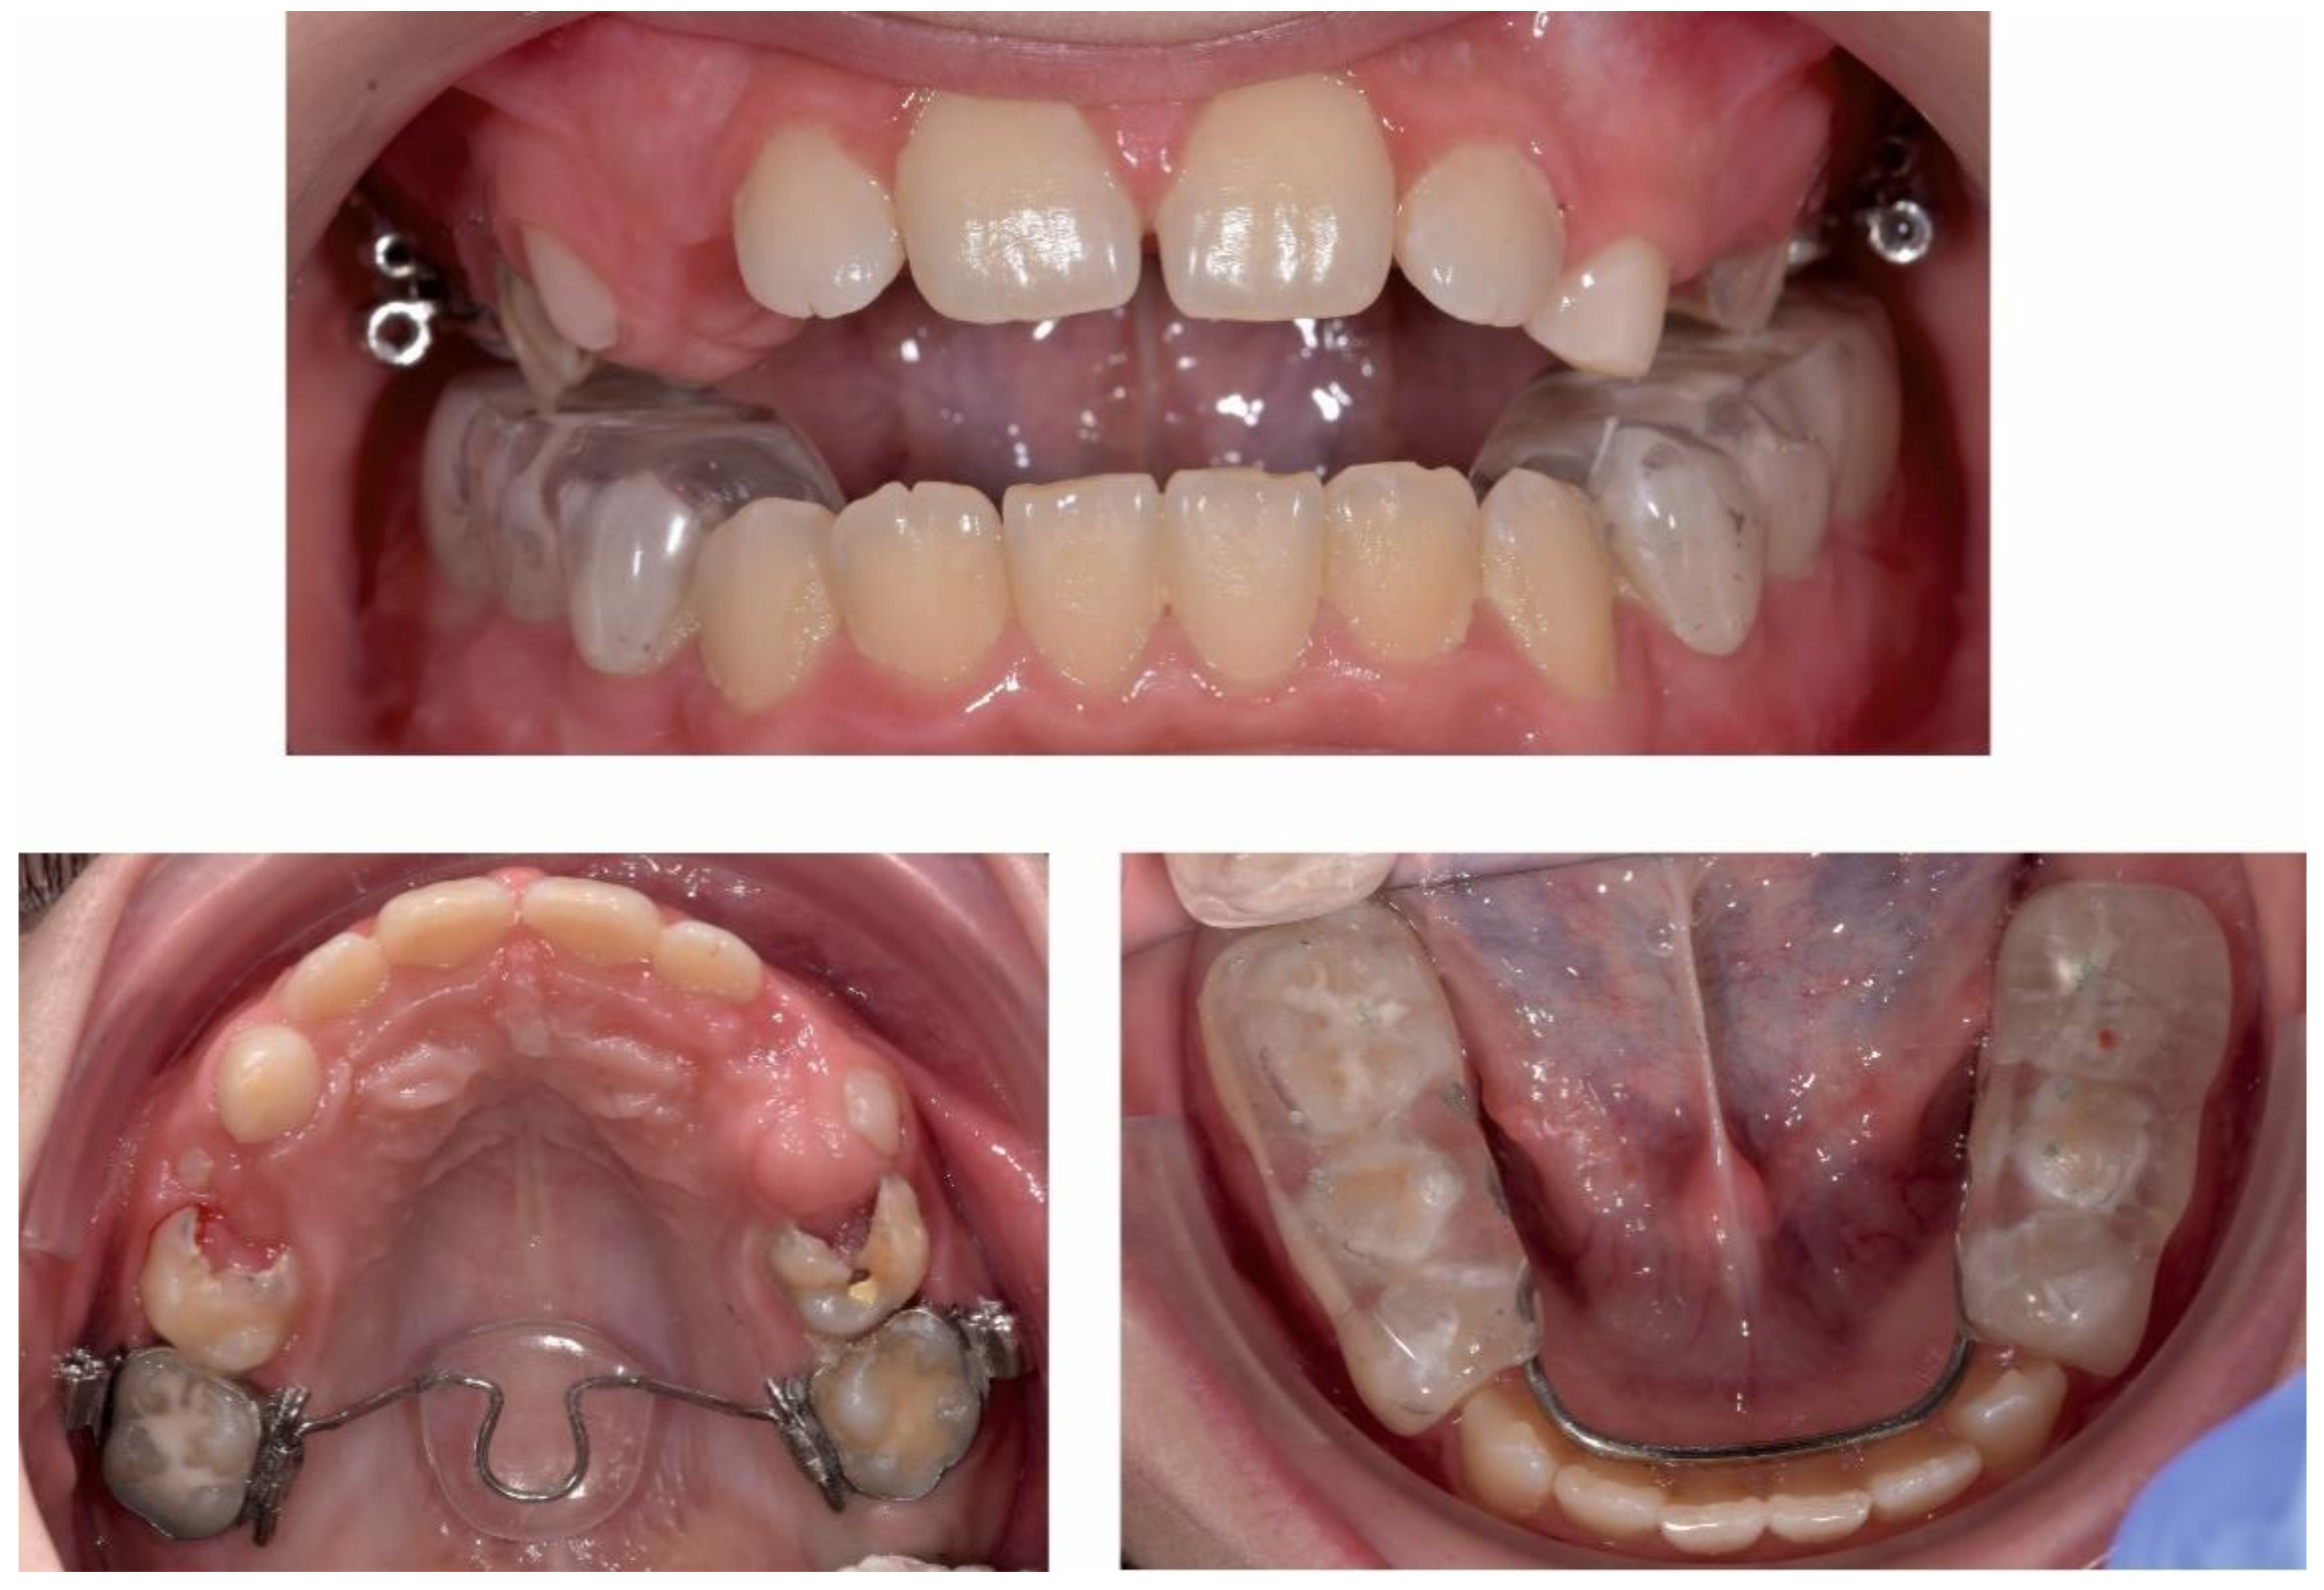

2.3.1. First Treatment Phase—2016—TMJ Splint Therapy

2.3.2. Second Phase of Treatment—2017—Bite-Blocks and Transpalatal Arch